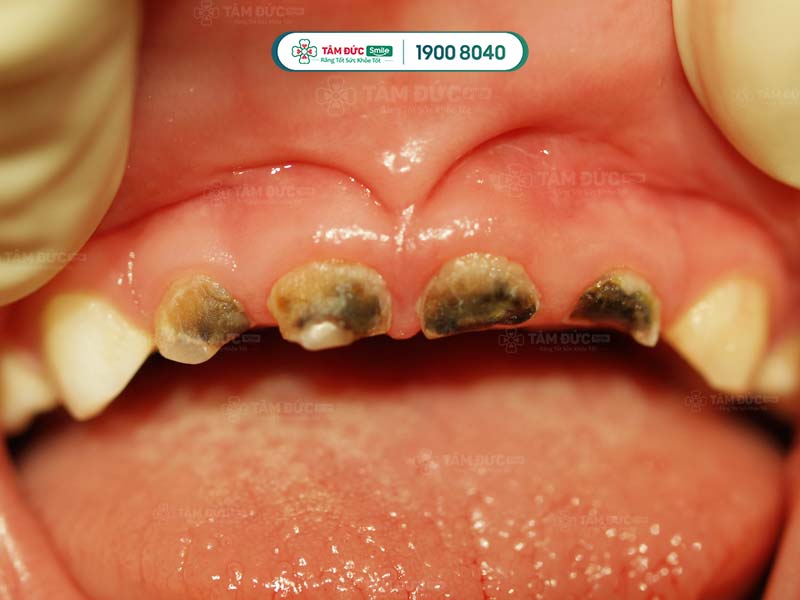

RĂNG TRẺ BỊ ĐEN: NGUYÊN NHÂN TỪ ĐÂU? KHẮC PHỤC NHƯ THẾ NÀO?

Răng trẻ bị đen